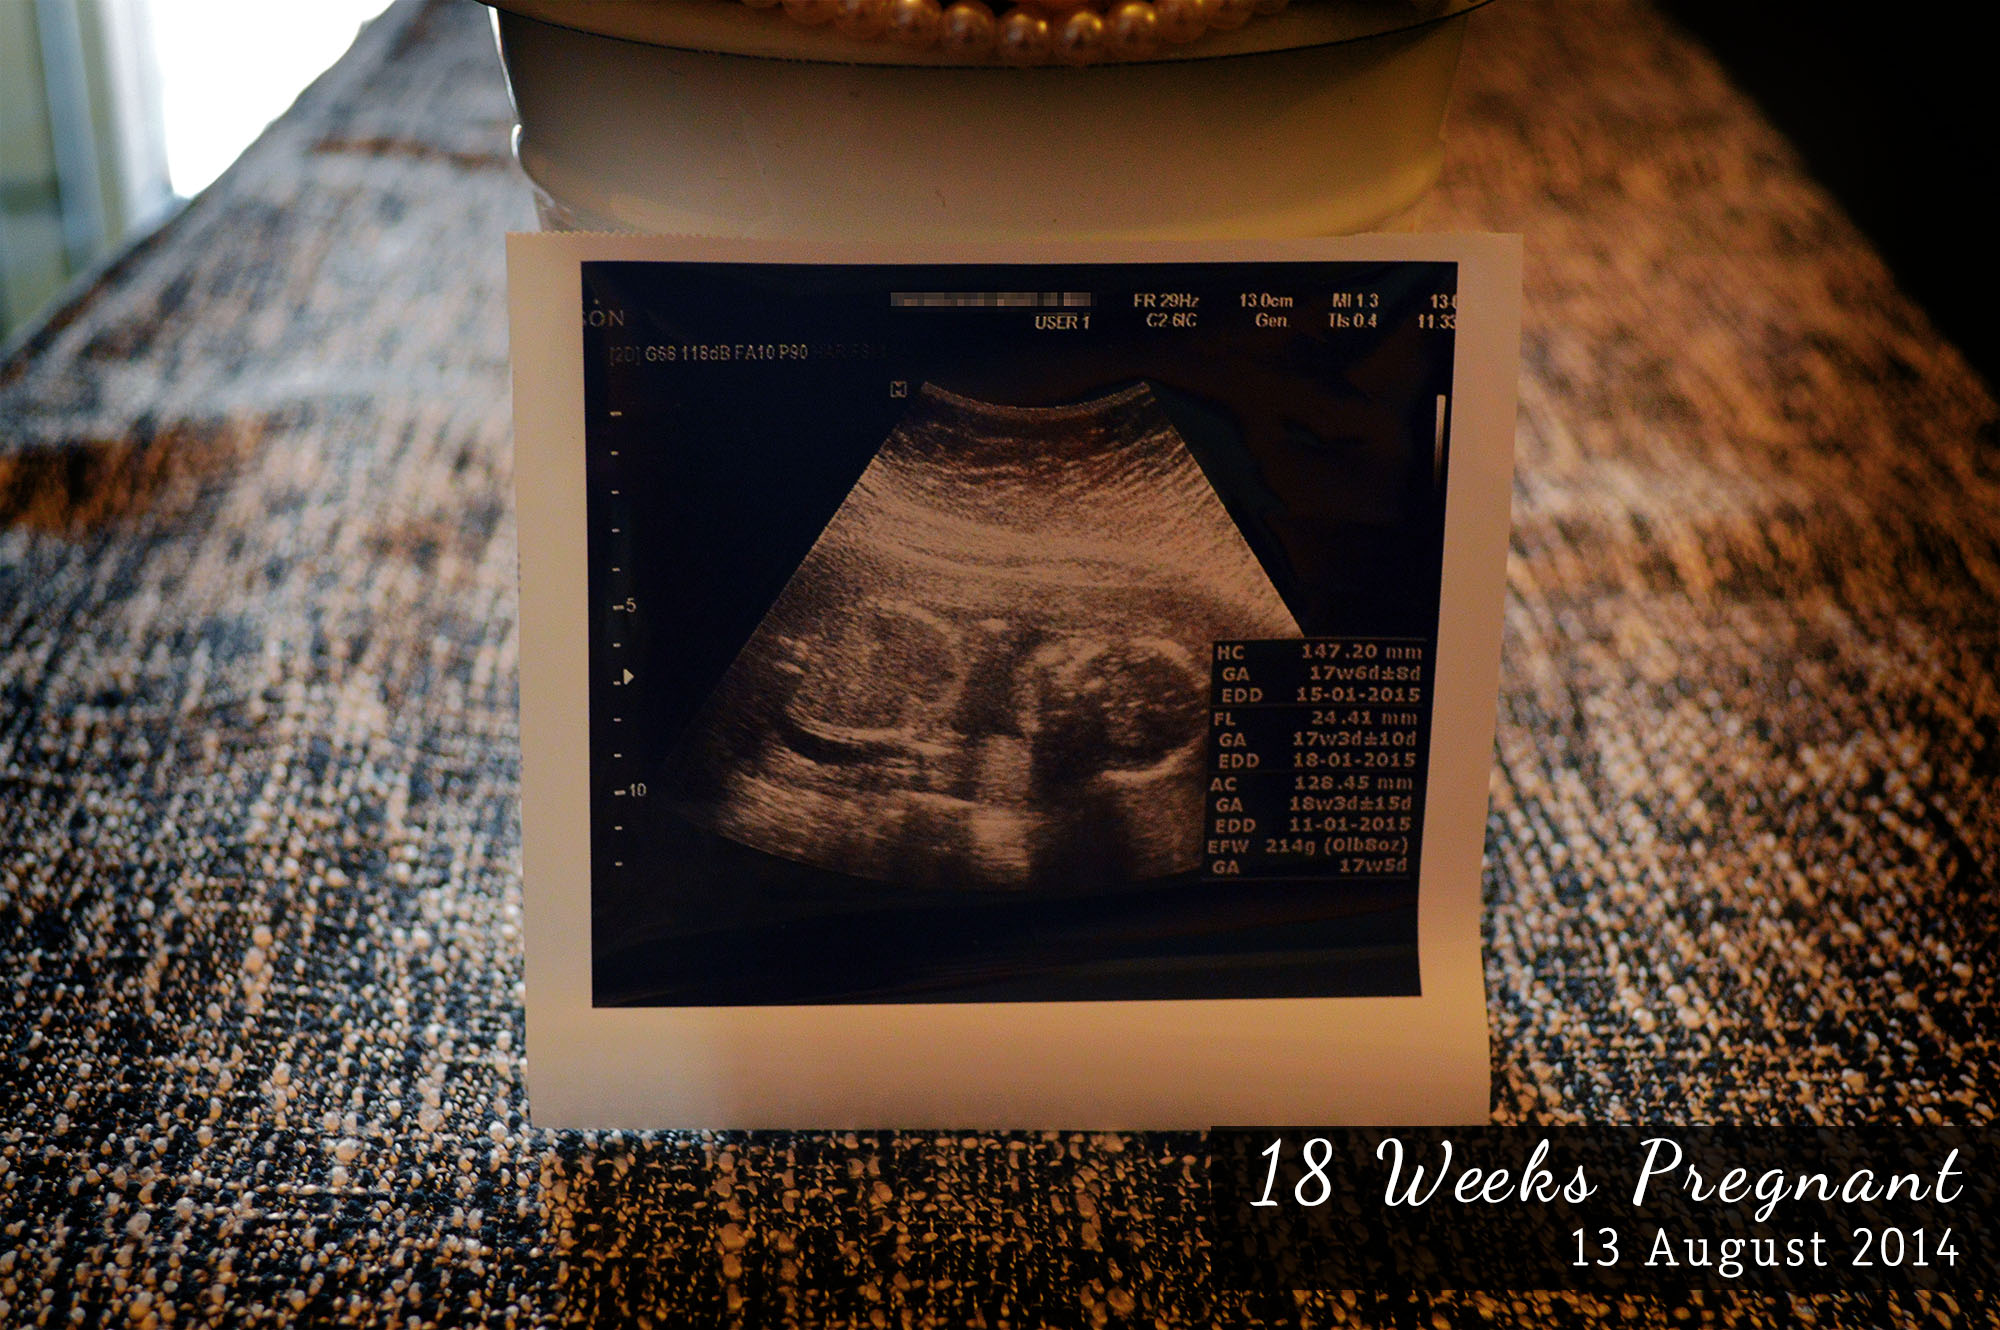

I was compiling all my Ultrasound scan pictures earlier and was amazed at how fast baby is growing.

18 weeks

6 weeks later, all your facial features are there. You can now clench your fist.